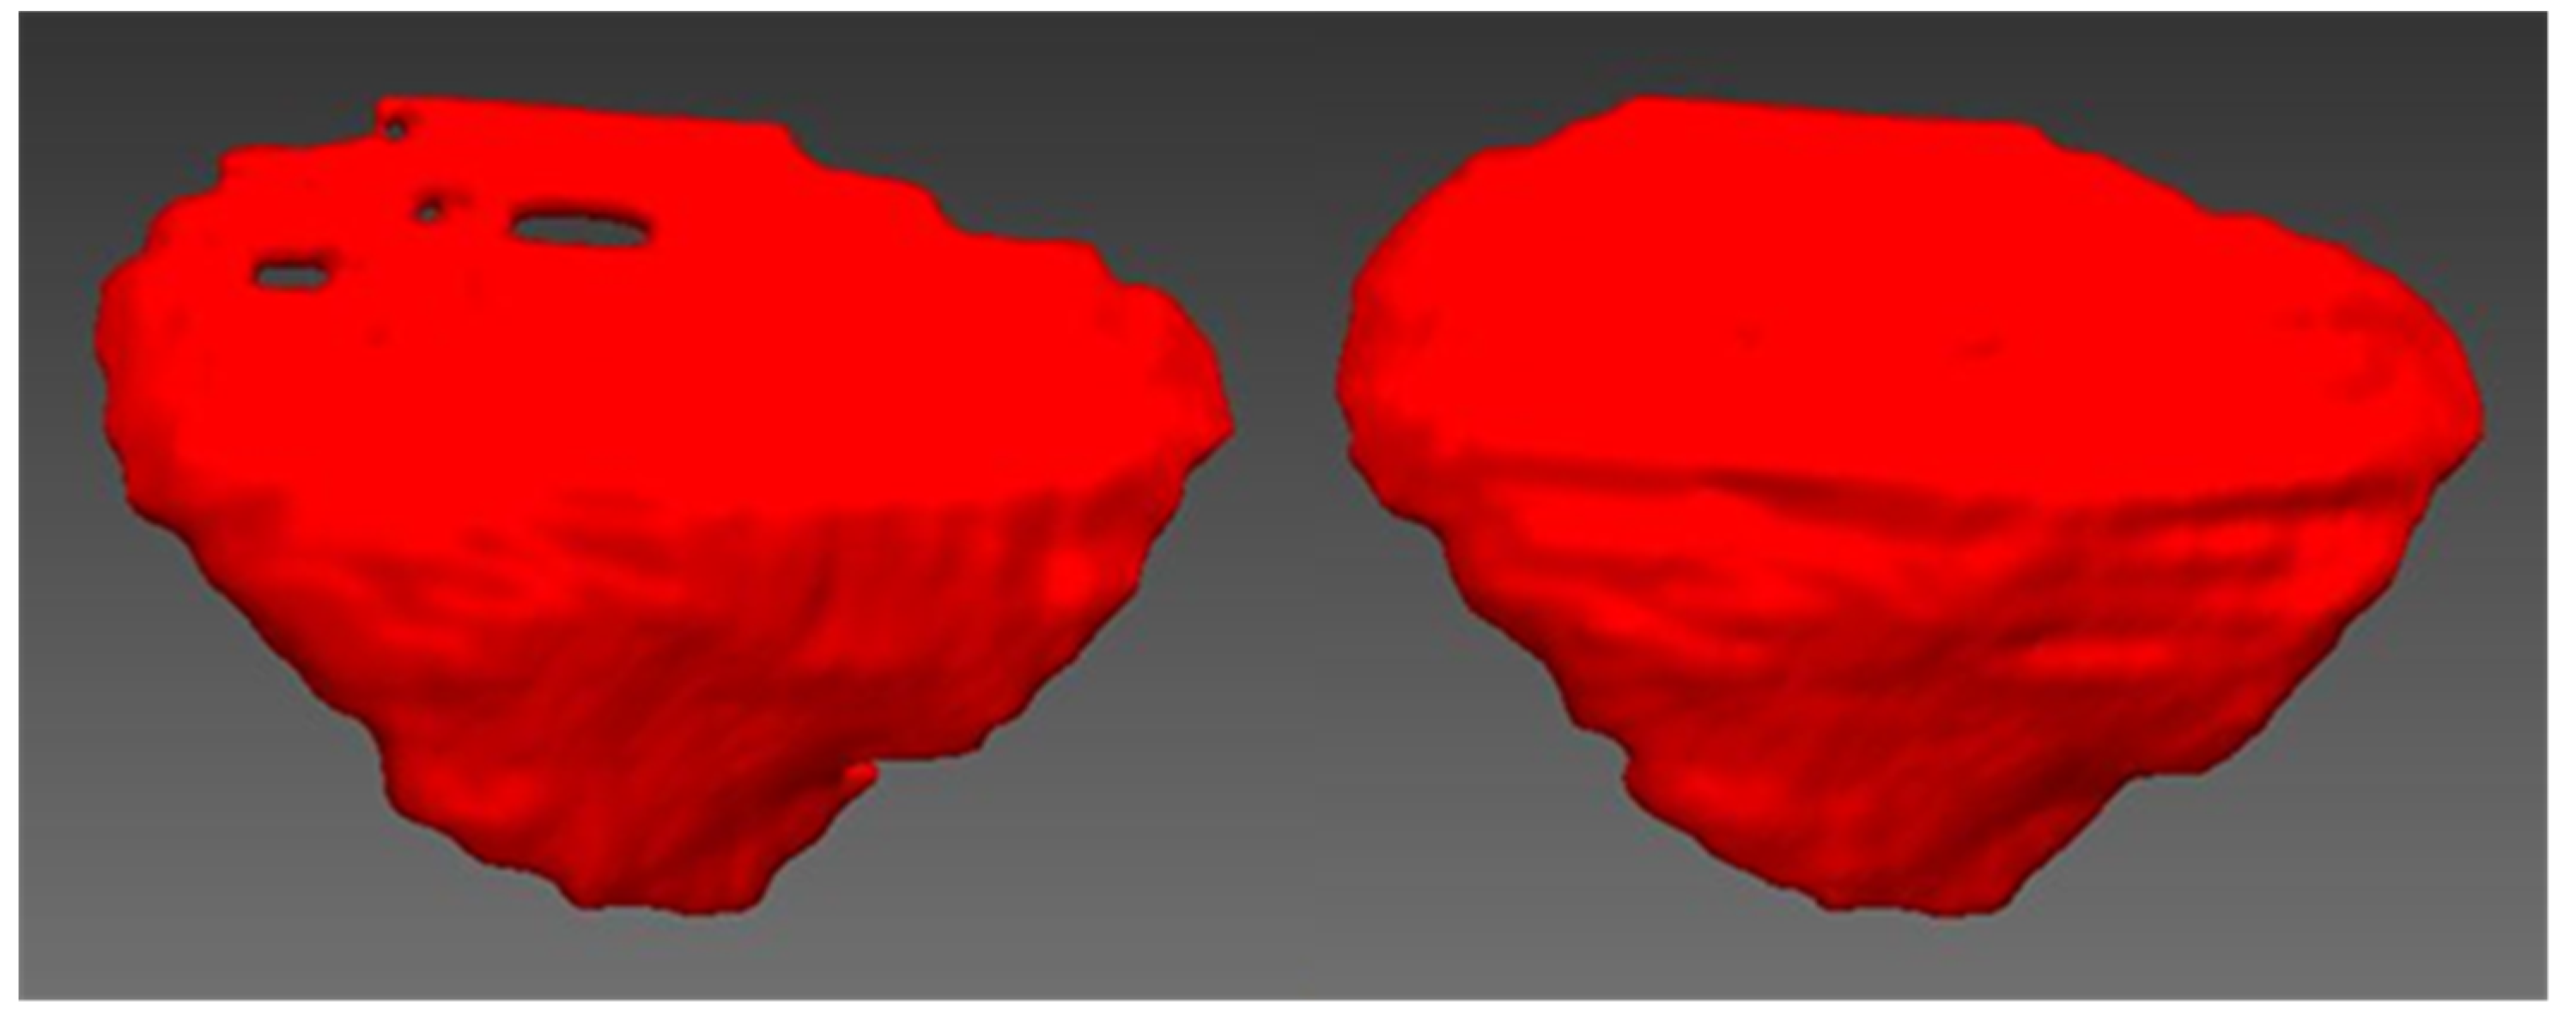

2.1. Design of Cranial Implants Using 3-Matic Software

2.2. Design of Cranial Implants Using MITK Software